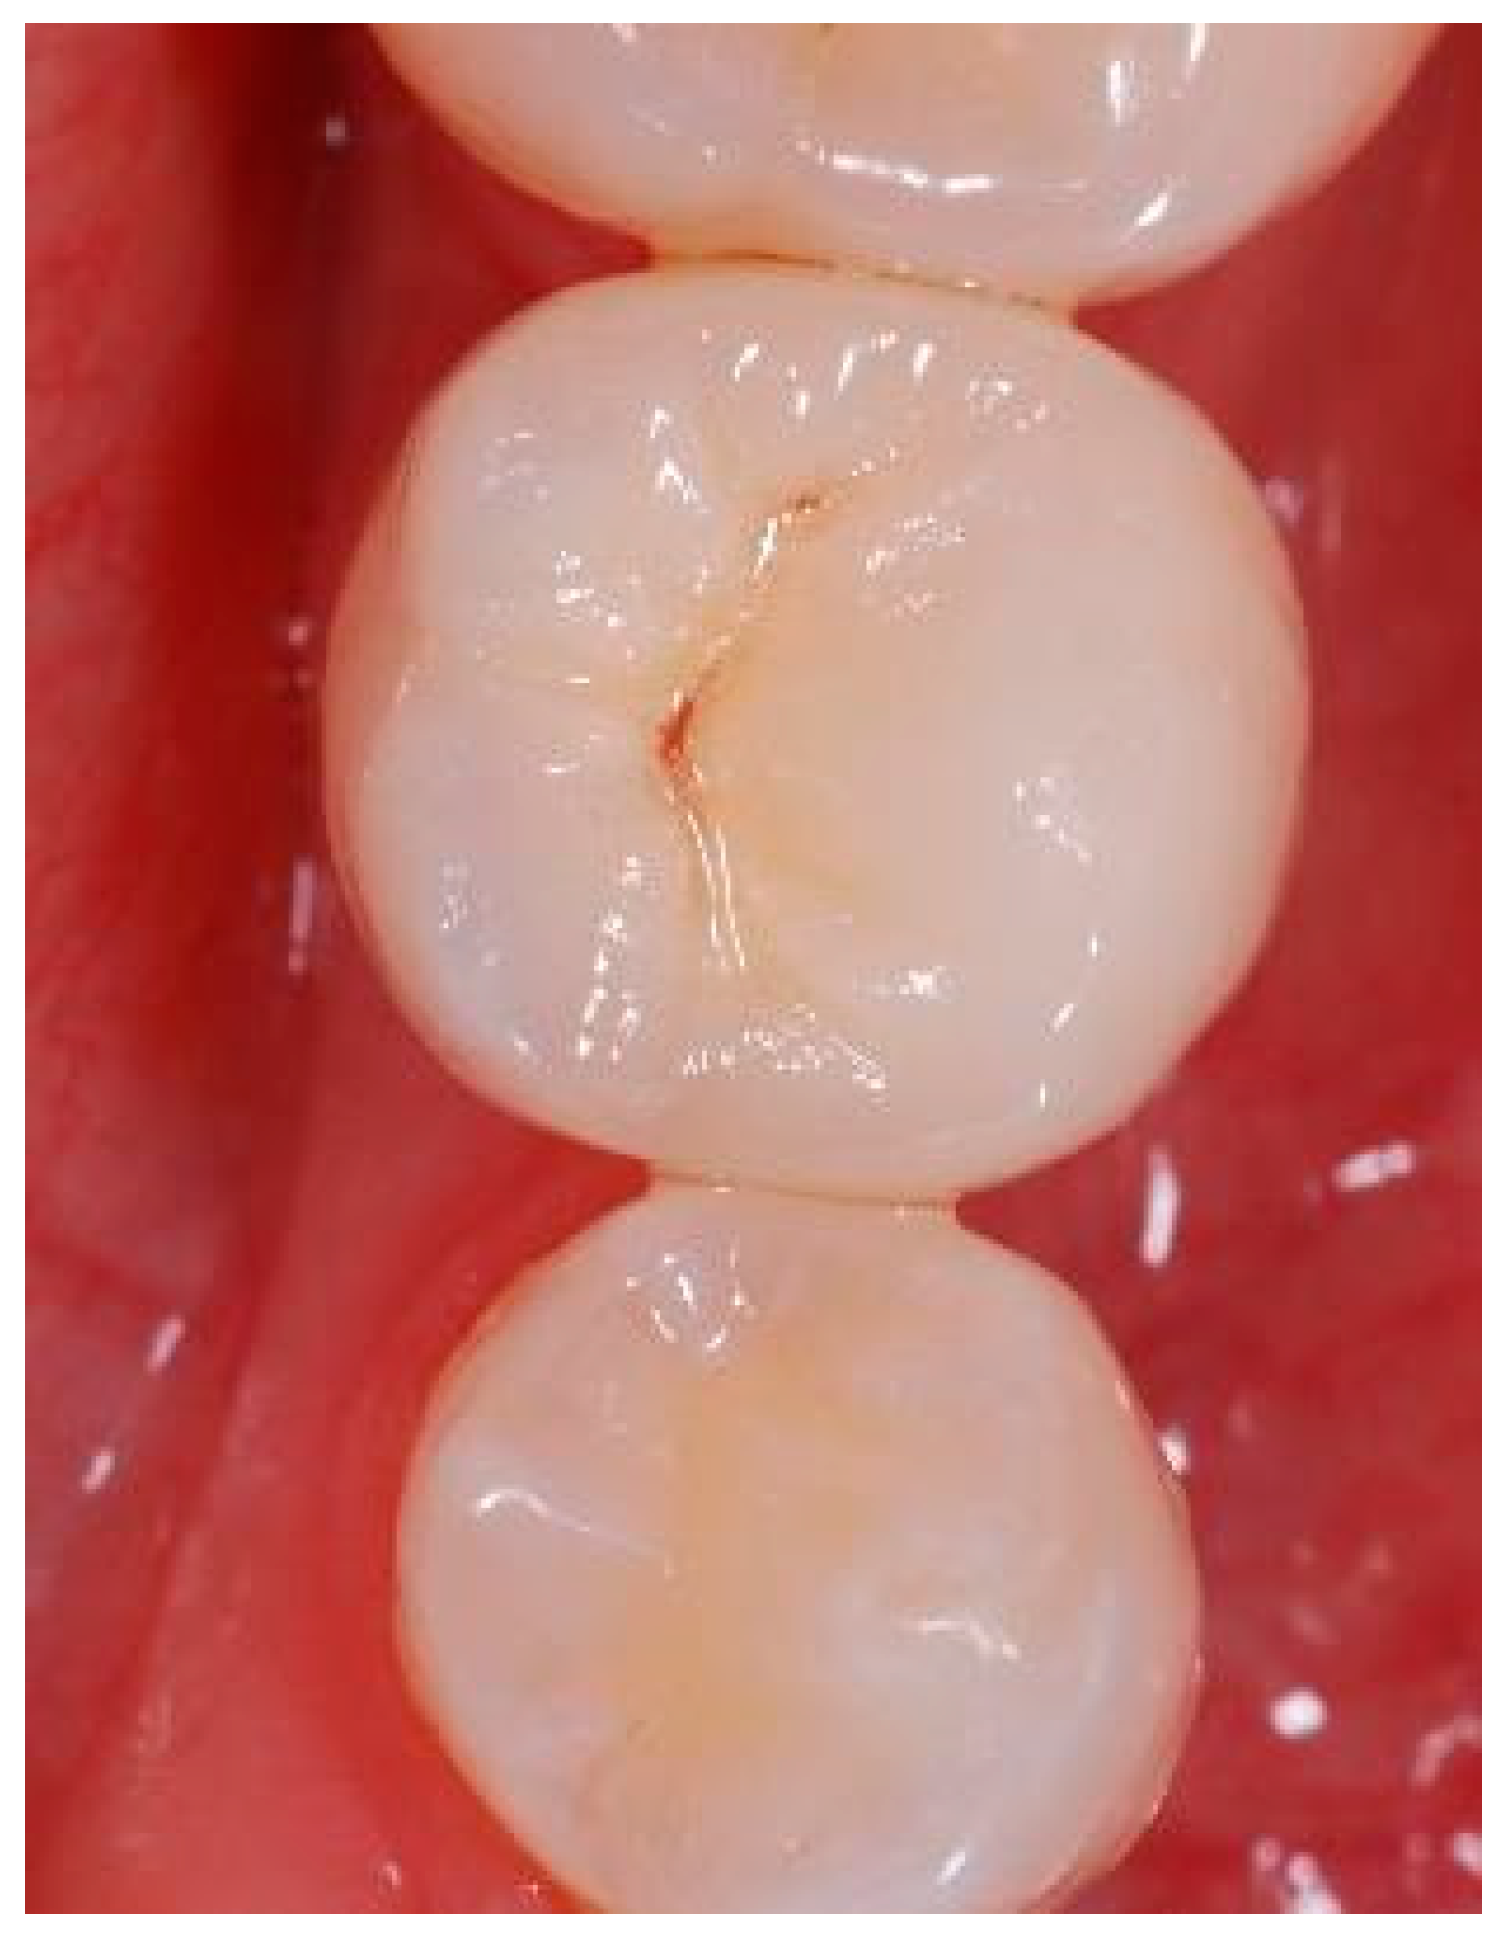

Appendix A. Exemplary Photographs and Radiographs from a Patient at Different Examination Time Points and a Positive Outcome